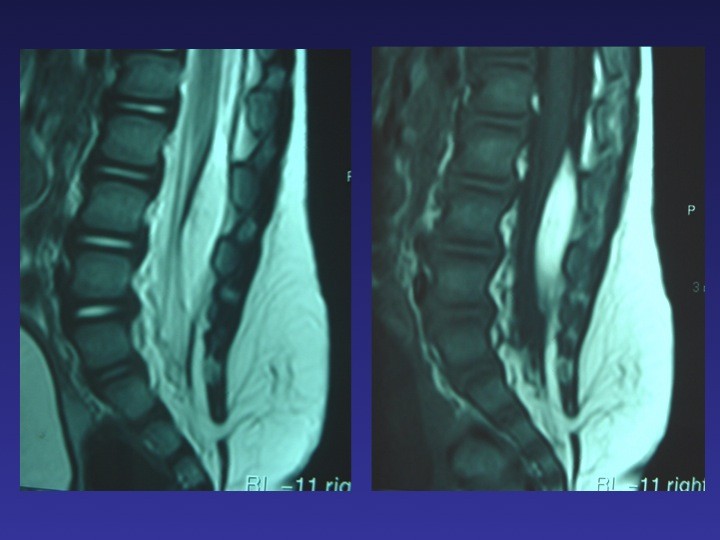

TABLE RONDE – La moelle attachée de l’enfant et de l’adolescent : diaporama 1